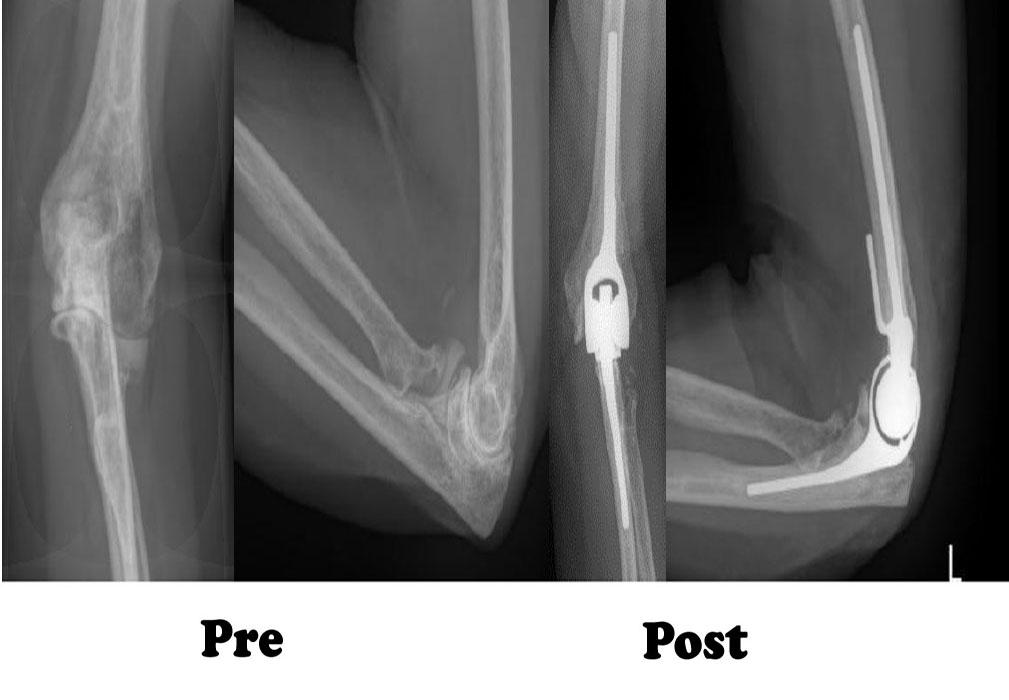

In total elbow replacement surgery, the damaged parts of the humerus and ulna are replaced with artificial components. The artificial elbow joint is made up of a metal and plastic hinge with two metal stems. The stems fit inside the hollow part of the bone called the canal.

This type of arthritis can follow a serious elbow injury. Fractures of the bones that make up the elbow, or tears of the surrounding tendons and ligaments may cause damage to the articular cartilage over time. This causes pain and limits elbow function.

To reach the elbow joint, your surgeon will make an incision (cut), usually at the back of the elbow. After making the incision, your surgeon will gently move muscles aside to get access to the bone. After removing scar tissue and spurs around the joint, your surgeon will prepare the humerus to fit the metallic piece that will replace that side of the joint. The same preparation is done for the ulna.The replacement stems are placed into the humerus and ulna bones, and kept in place with a bone cement. The two stems are connected by a hinge pin. After the wound is closed, a padded dressing is then placed to protect the incision while it heals. Some surgeons will place a temporary tube in the joint to drain the surgical fluid. This tube can be easily removed in your hospital room within the first few days after surgery.